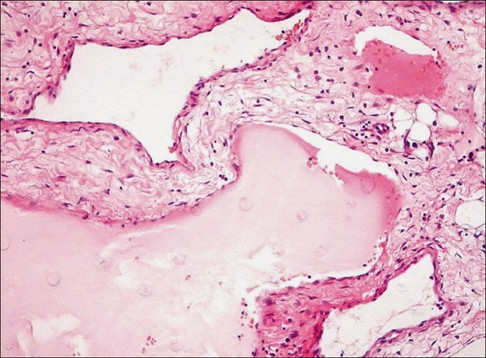

Características Histopatológicas:

No linfangioma cavernoso há dilatação dos vasos linfáticos localizados logo abaixo da superfície epitelial, podendo apresentar agregados linfoides a sua parede por causa da infiltração dos vasos no tecido mole adjacente. O endotélio que envolve o vaso é fino e os espaços contêm fluido proteináceo e linfócitos ocasionais, além de hemácias.

Disponível em: http://imgkid.com/lymphangioma-histology.shtml